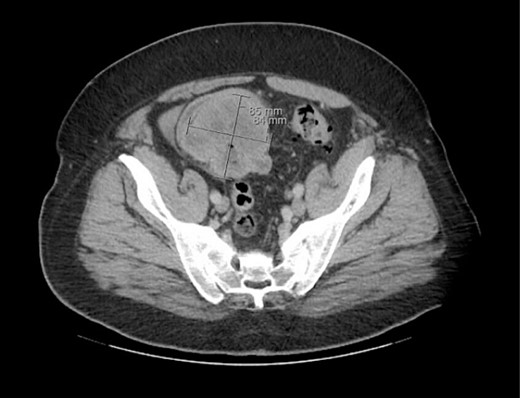

The patient was initially managed nonoperatively with conservative measures including nasogastric (NG) tube decompression, pain control, and serial abdominal exams. Surgery was consulted once CT imaging was obtained (Figs 1–3) and recommended that the patient undergo surgery to resect the identified mass and relieve the obstruction. During the surgical exploration, a mass originating from the terminal ilium was identified that was densely adhered to the peritoneum, bladder, and sigmoid colon, requiring careful dissection. The mass, three lymph nodes, and 29 cm of associated small bowel segment was resected with grossly negative margins, with the mass measuring 7 cm × 8 cm × 9.5 cm. A side-to-side anastomosis was created and the specimens were sent to pathology for further investigation. Postoperatively the patient was hospitalized for 7 days for pain control and monitoring. On postoperative day eight he was discharged with follow up appointments with oncology, general surgery, and a referral to an academic cancer center.

Initial CT imaging, sagittal cut, showing necrotic mass causing small bowel obstruction.